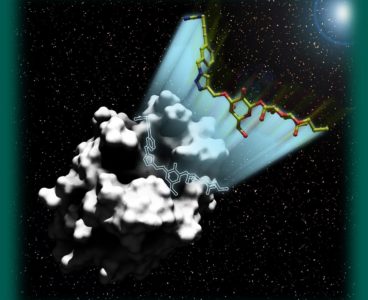

Cancer Detection With Sugar Molecules

Galectins are a family of proteins that have become a promising source of cancer research in recent years. A representative thereof is galectin-1. It sits on the surface of all human cells; on tumor cells, however, it occurs in enormous quantities. This makes it an interesting target for diagnostics and therapy. “Among other things, it…